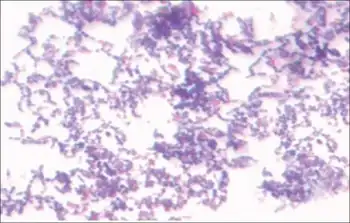

Stain of S. mutans in thioglycollate broth culture. | |